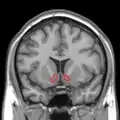

Nucleus accumbens

Nucleus accumbens of the mouse brain